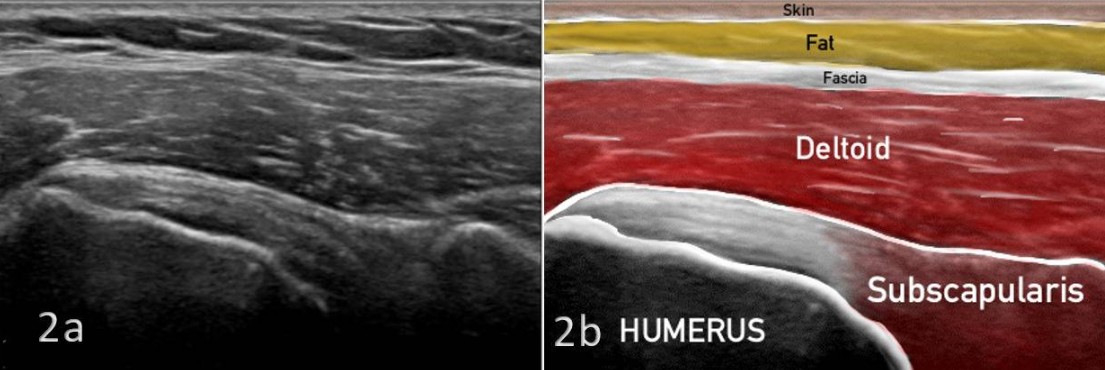

En un corte longitudinal al tendón subescapular, la imagen que obtendrás es la siguiente:

Los detalles anatómicos de este corte ecográfico corresponden a: